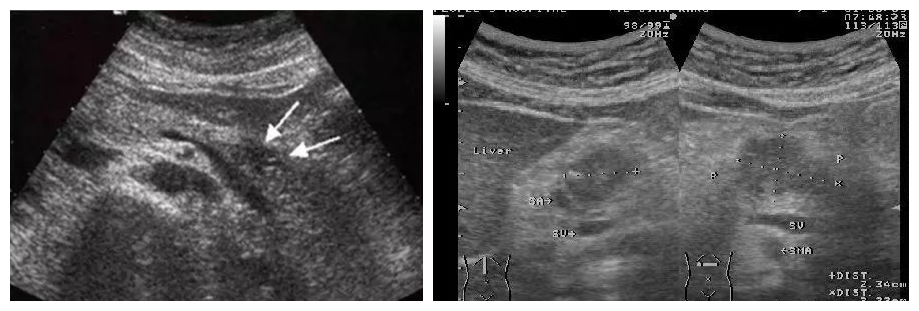

(一) 声像图特征

1.在胰腺癌所在部位的胰腺内出现低回声肿块,边界不整齐,轮廓不清晰,肿瘤常向周围组织呈“蟹足样”浸润。肿瘤较大时,癌瘤中心产生液化、坏死而呈混合性肿块。

图片

2.胰腺癌压迫周围脏器及血管,亦可压迫胆管、胰管引起梗阻。

3.晚期胰腺癌,肝内出现转移性肿瘤,胰腺周围、腹主动脉旁出现转移性淋巴结肿大及腹水。

(右图为胰腺癌肝内转移)

(二) 超声检查的临床意义

超声对于肿块大于1cm并向胰腺外突出的胰腺癌诊断的正确率较高,但对于肿块小于1cm且不向胰腺外突出的胰腺癌,尤其是胰腺钩突癌、胰体、尾癌诊断的敏感性和特异性均较差。虽然如此,但是由于胰头癌在整个胰腺癌中占3/4,而且超声具有灵活简便,无辐射、费用低廉等众多优点,所以仍然是作为诊断及早期胰腺癌筛选的首选方法之一。